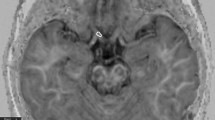

DTI was preprocessed for denoising and corrected for eddy current and motion artifacts using MRtrix3 software (http://www.mrtrix.org) based on published methods15,16,17,18,19. The susceptibility-induced off-resonance field and subject head motion was estimated using two pairs of b0 images with distortions in opposite directions. One corrected b0 image was generated, and then this estimated field was applied to correct the entire diffusion data. This method is based on registering the individual volumes of the diffusion data set to a model-free prediction to account for unique eddy current distortions present in each volume and any subject movement between the acquisition of successive volumes20. Subsequent processing was performed using the mrDiffusion implemented in Vistasoft (https://github.com/vistalab/vistasoft). The corrected diffusion data, as a set of 49 images, were co-registered to the anterior commissure—posterior commissure aligned T1 image using a rigid-body mutual information algorithm. Diffusion-weighting gradient directions were reoriented by applying the same transformation used on the diffusion-weighted images and resampled to 2 mm isotropic voxels using trilinear interpolation. Finally, the tensors were estimated to compute FA, MD, RD, and AD using a least-squares algorithm with bootstrapping for 500 times21. Overview of the DTI analysis and details of diffusion measures for ONs are illustrated in Fig. 1. Plotting tensor model and fiber tract on MRI was done using FSLeyes (v0.34.2) https://fsl.fmrib.ox.ac.uk/fsl/fslwiki/FSLeyes) and Matlab Brain Anatomy (MBA, https://github.com/francopestilli/mba). The main diffusion properties for FA and RD in our analysis are visualized in Fig. 2B.

Overview of diffusion tensor imaging (DWI) analysis. (A) Preprocessing of raw DWI data. A set of 50 images was acquired from each participant, including 48 sampling directions and two b0 images of anteroposterior (AP) and posteroanterior (PA) phase-encoding directions (i). One corrected b0 image was generated, and the entire diffusion data was applied by estimating artifacts from two pairs of b0 images (ii). Finally, a set of 49 images was co-registered to the T1 image (iii). (B) Diffusion tensor model. To represent the optic nerve in the axial (i), sagittal (ii), and coronal (iii) views on the FA image, diffusion directionality was color-coded with green representing anterior–posterior directions, red representing left–right directions, and blue representing superior-inferior directions for a single subject using FSL eyes. A close-up view of 3 × 3 voxels of the optic nerve behind the eye globe in the axial (iv), three voxels in the sagittal (v), and three voxels in the coronal views (vi). The diffusion tensor D was estimated from a set of DWIs. The three orthotropic axes of a diffusion ellipsoid can be determined by the decomposition of the tensor into eigenvectors and eigenvalues (vii). (C) Tensor-derived diffusion measures. Cropped image of the fractional anisotropy (FA) (i), mean diffusivity (MD) (ii), axial diffusivity (AD) (iii), and radial diffusivity (RD) (iv). FA values are bounded between zero (a perfect sphere) and one (an infinitely long cigar shape). MD is the mean of the eigenvalues of the diffusion tensor. AD indicates an eigenvalue of λ1, which is diffusivity along the principal axes, while RD is diffusivity along non-principal axes by averaging the eigenvalues of λ2 and λ3. (D) Optic nerve fiber tractography. Two spherical regions of interest (ROIs) are placed posterior to the globe of the eye and in the orbital apex at the center of the annulus of Zinn to identify the optic nerve pathway. Placement of the two ROIs overlaid on T1 (i) and FA image (ii). Visualization for cleaned optic nerve tractography (iii) and a central fiber in the optic nerve passing through the ROI (iv).

Visualization of the average peripapillary retinal nerve fiber layer (RNFL) thickness, diffusion measures, and tract profiles of six patients with optic nerve atrophy. (A) A plot indicating the average temporal-superior-nasal-inferior-temporal RNFL thickness of optic nerve head, measured at a circle with a diameter of 3.4 mm centered on the disc by optical coherence tomography. The RNFL thickness of the atrophic eyes (solid line) was significantly reduced compared to that of contralateral non-affected eyes (dashed line). (B) Optic nerve pathway mapping by the average fractional anisotropy and radial diffusivity (\(\upmu\)m2/s) values for six atrophic optic nerves (ONs) and six non-affected ONs are presented in the left and right, respectively. (C) Average tract profiles across the ONs of six atrophic (red) eyes and six non-affected (gray) eyes plotted by mean lines with standard deviation and each node marked with dotted lines. Five nodes nearest the optic nerve head were excluded from the analysis and are shaded white in the graph.

Group differences in diffusion measures of the ONs are shown in Fig. 3. FA of atrophic ON was significantly lower than that of non-affected and control ONs (atrophic [A], 0.136 ± 0.059; non-affected [N], 0.384 ± 0.048; control [C], 0.389 ± 0.053; A vs N, P < 0.001; A vs C, P < 0.001). Also, MD and RD of atrophic ONs were significantly higher than those of non-affected and control ONs (MD, A, 0.988 ± 0.247; N, 0.658 ± 0.058; C, 0.687 ± 0.079; A vs N, P = 0.010; A vs C, P = 0.002; RD, A, 0.920 ± 0.247; N, 0.510 ± 0.054; C, 0.532 ± 0.078; A vs N, P = 0.003; A vs C, P < 0.001). AD did not show significant differences between the groups (A, 1.123 ± 0.252; N, 0.955 ± 0.080; C, 0.998 ± 0.094; A vs N, P = 0.152; A vs C, P = 0.155). Figure 2B,C visualizes the significance differences in average FA and RD between atrophic and non-affected ONs. Figure 2C shows the average tract profiles across the ONs.